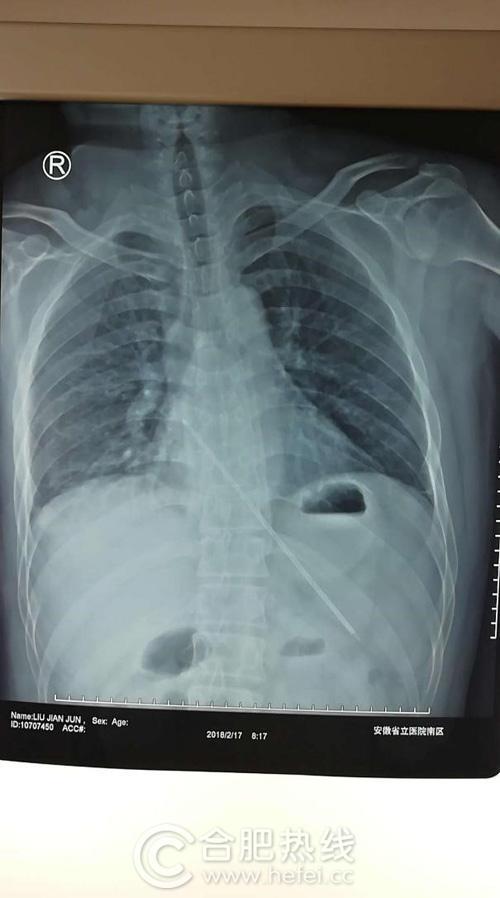

柳常青立即安排做了检查,检查结果让他立刻意识到问题的严重性:这根长长的金属针戳破食管进入胸腔,极可能导致食管纵隔瘘;金属针所在区域为心脏大血管区域,极有可能导致血管破裂,继而导致致命性的大出血;这种金属异物在体内留存一个月之久,腐蚀到何种程度、是否已经断裂、胸腔是否有感染?这么长的金属针如何取出?手术途径是经胸还是经腹?手术方式是微创还是开放?

术中取出的金属针竟有18cm长,外面包了一层塑料,而整个手术切口却仅为3个1.5cm长的微孔,医生边将针折弯边小心翼翼地取出,术中出血仅10ml!